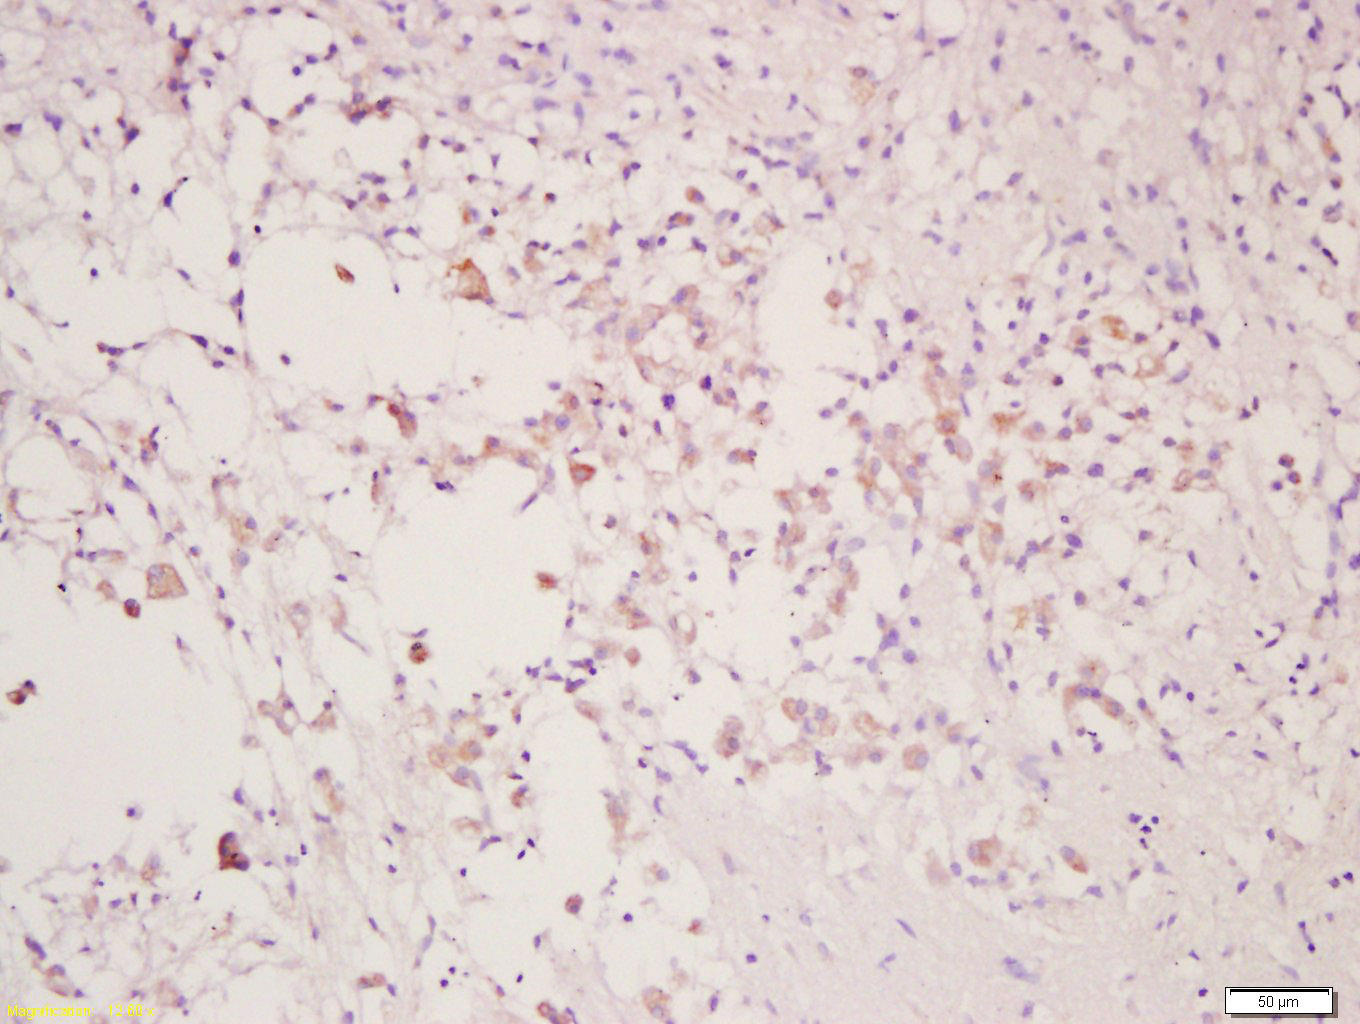

Tissue/cell: rat injured brain; 4% Paraformaldehyde-fixed and paraffin-embedded; Antigen retrieval: citrate buffer ( 0.01M, pH 6.0 ), Boiling bathing for 15min; Block endogenous peroxidase by 3% Hydrogen peroxide for 30min; Blocking buffer (normal goat serum,C-0005) at 37℃ for 20 min; Incubation: Anti-CLEC9A Polyclonal Antibody, Unconjugated(bs-13620R) 1:200, overnight at 4°C, followed by conjugation to the secondary antibody(SP-0023) and DAB(C-0010) staining